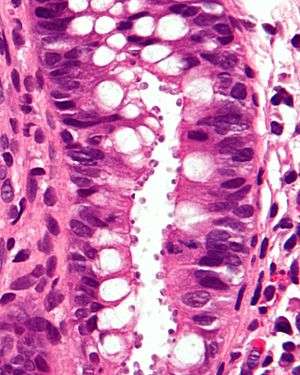

| Micrograph showing cryptosporidiosis. The cryptosporidium are the small, round bodies in apical vacuoles on the surface of the epithelium. H&E stain. Colonic biopsy. | |

Other staining techniques include acid-fast staining,[22] which will stain the oocysts red.[21] One type of acid-fast stain is the Kinyoun stain.[17] Giemsa staining can also be performed.[18] Part of the small intestine can be stained with hematoxylin and eosin (H & E), which will show oocysts attached to the epithelial cells.[21]